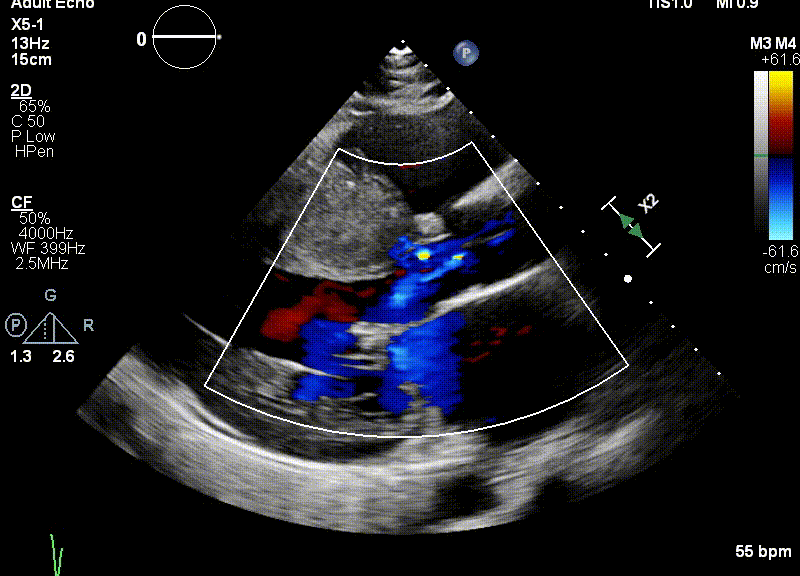

三位患者均患肥厚型梗阻性心肌病多年,因药物治疗效果不佳而到浙江大学医学院附属第二医院就诊。超声提示三位患者的室间隔呈非对称增厚,造成左室流出道梗阻。经团队评估决定进行超声引导下Liwen术式对室间隔进行消融。

2022年7月1日在浙江大学医学院附属第二医院导管室,应用Liwen RF射频消融系统经心尖到达肥厚室间隔进行射频消融,术后即刻超声显示靶区消融充分,术后即可左室流出道压差显著降低。

患者为一名40岁的女性。超声提示患者室间隔最大厚度为31.3mm,静息压差为102mmHg,负荷状态下为146mmHg。二尖瓣呈SAM征伴有少量反流。